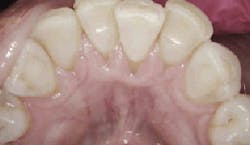

Taken after probing on July 7, 2016. Image courtesy of Perfect Teeth–Frank Lloyd Wright.

On July 7, 2016, when the patient returned, bleeding was reduced from 101 sites to seven sites, and deep pockets decreased from 37% to just 2%. The patient was then asked to incorporate the trays into her regular home care, using them once a day for 15 minutes.